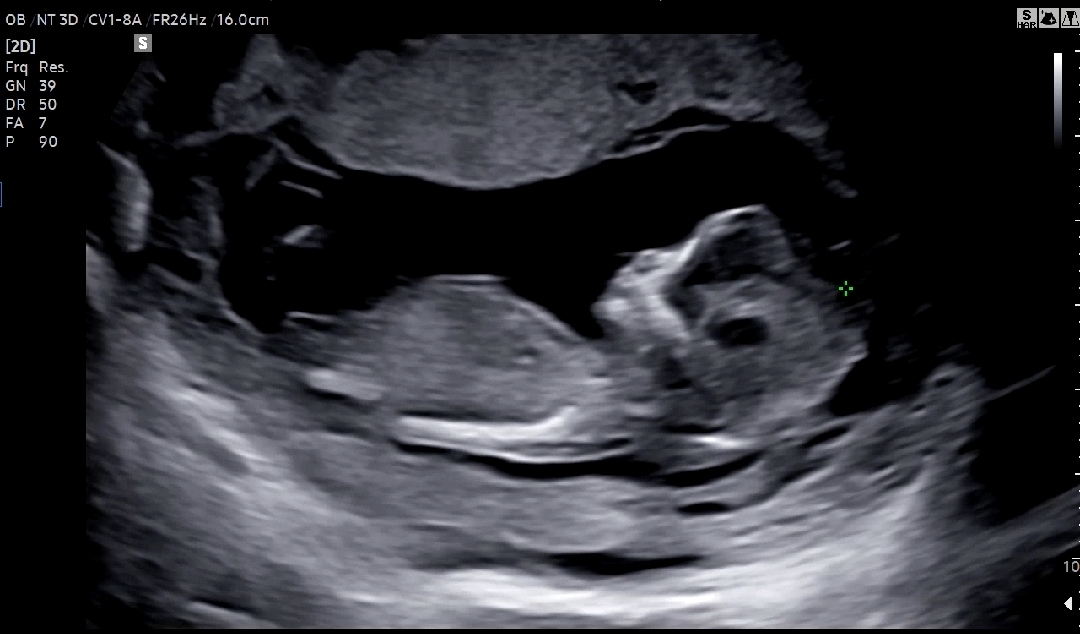

12주4일차 각도법 봐주세요🙏

오늘 1차기형아 검사하고 왔는데 정상이라고 하셔서 마음이 놓이네요🙂 12주4일차 고수님들의 각도법 부탁드립니다!